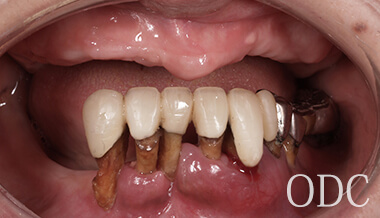

術 前

初診時87歳、男性。上顎は歯周病により残存歯を長期的に機能させることが困難と判断し、全て抜歯。出来る限り早期の咬合機能の回復と審美性の実現が求められ、上顎は「4本のインプラントで失った全ての歯を固定し、手術当日から噛む機能を回復させることが可能」なオールオン4という術式を選択。オールオン4は「治療期間」「経済性」「審美性」「外科的侵襲」などのあらゆる負担を軽減した全く新しいコンセプトの画期的なインプラント治療です。 下顎の欠損部位に対しても、術前の診査診断をしっかり行い合計5本のインプラントを埋入しました。

術前・術後のパノラマX線写真です。上顎(オールオン4)は4本のインプラントにチタンフレームの上部構造が固定されているのがおわかりになると思います。下顎のインプラント埋入部位、上顎のインプラントの本数、再度写真をご覧いただくと、とてもインプラントが埋入されているとわからない程の外観、下顎の残存歯(元々の自分の歯)とも区別がつかない審美性が実現されています。